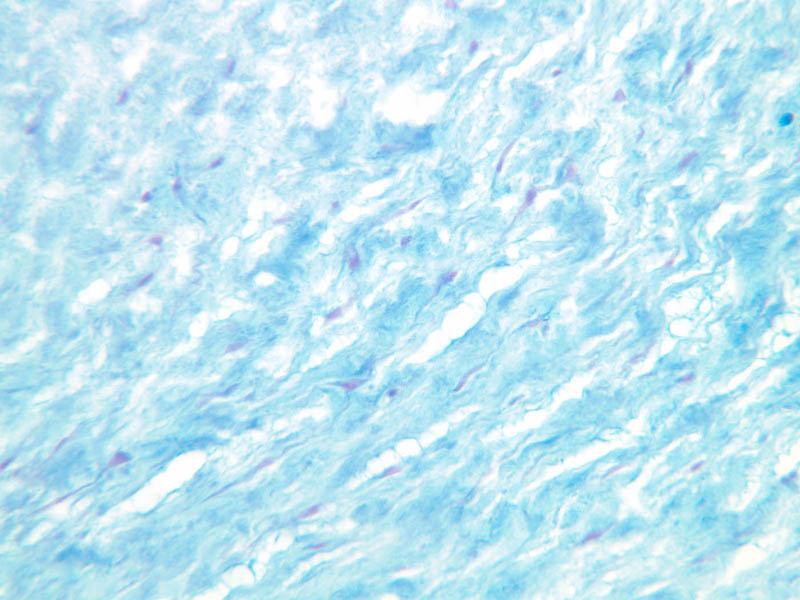

a95_mucous_ct_umbilical_cord_10x.jpgjpg a95_mucous_ct_umbilical_cord_10x.jpg manage 125 K 31 May 2007 - 22:40 AshleyLPistorio 2 - A95, Umbilical Cord, 10x (Alcian Blue)

a95_mucous_ct_umbilical_cord_20x.jpgjpg a95_mucous_ct_umbilical_cord_20x.jpg manage 104 K 31 May 2007 - 22:40 AshleyLPistorio 3 - A95, Umbilical Cord, 20x (Alcian Blue)

a95_mucous_ct_umbilical_cord_2x.jpgjpg a95_mucous_ct_umbilical_cord_2x.jpg manage 109 K 31 May 2007 - 22:40 AshleyLPistorio 1 - A95, Umbilical Cord, 2.5x (Alcian Blue)